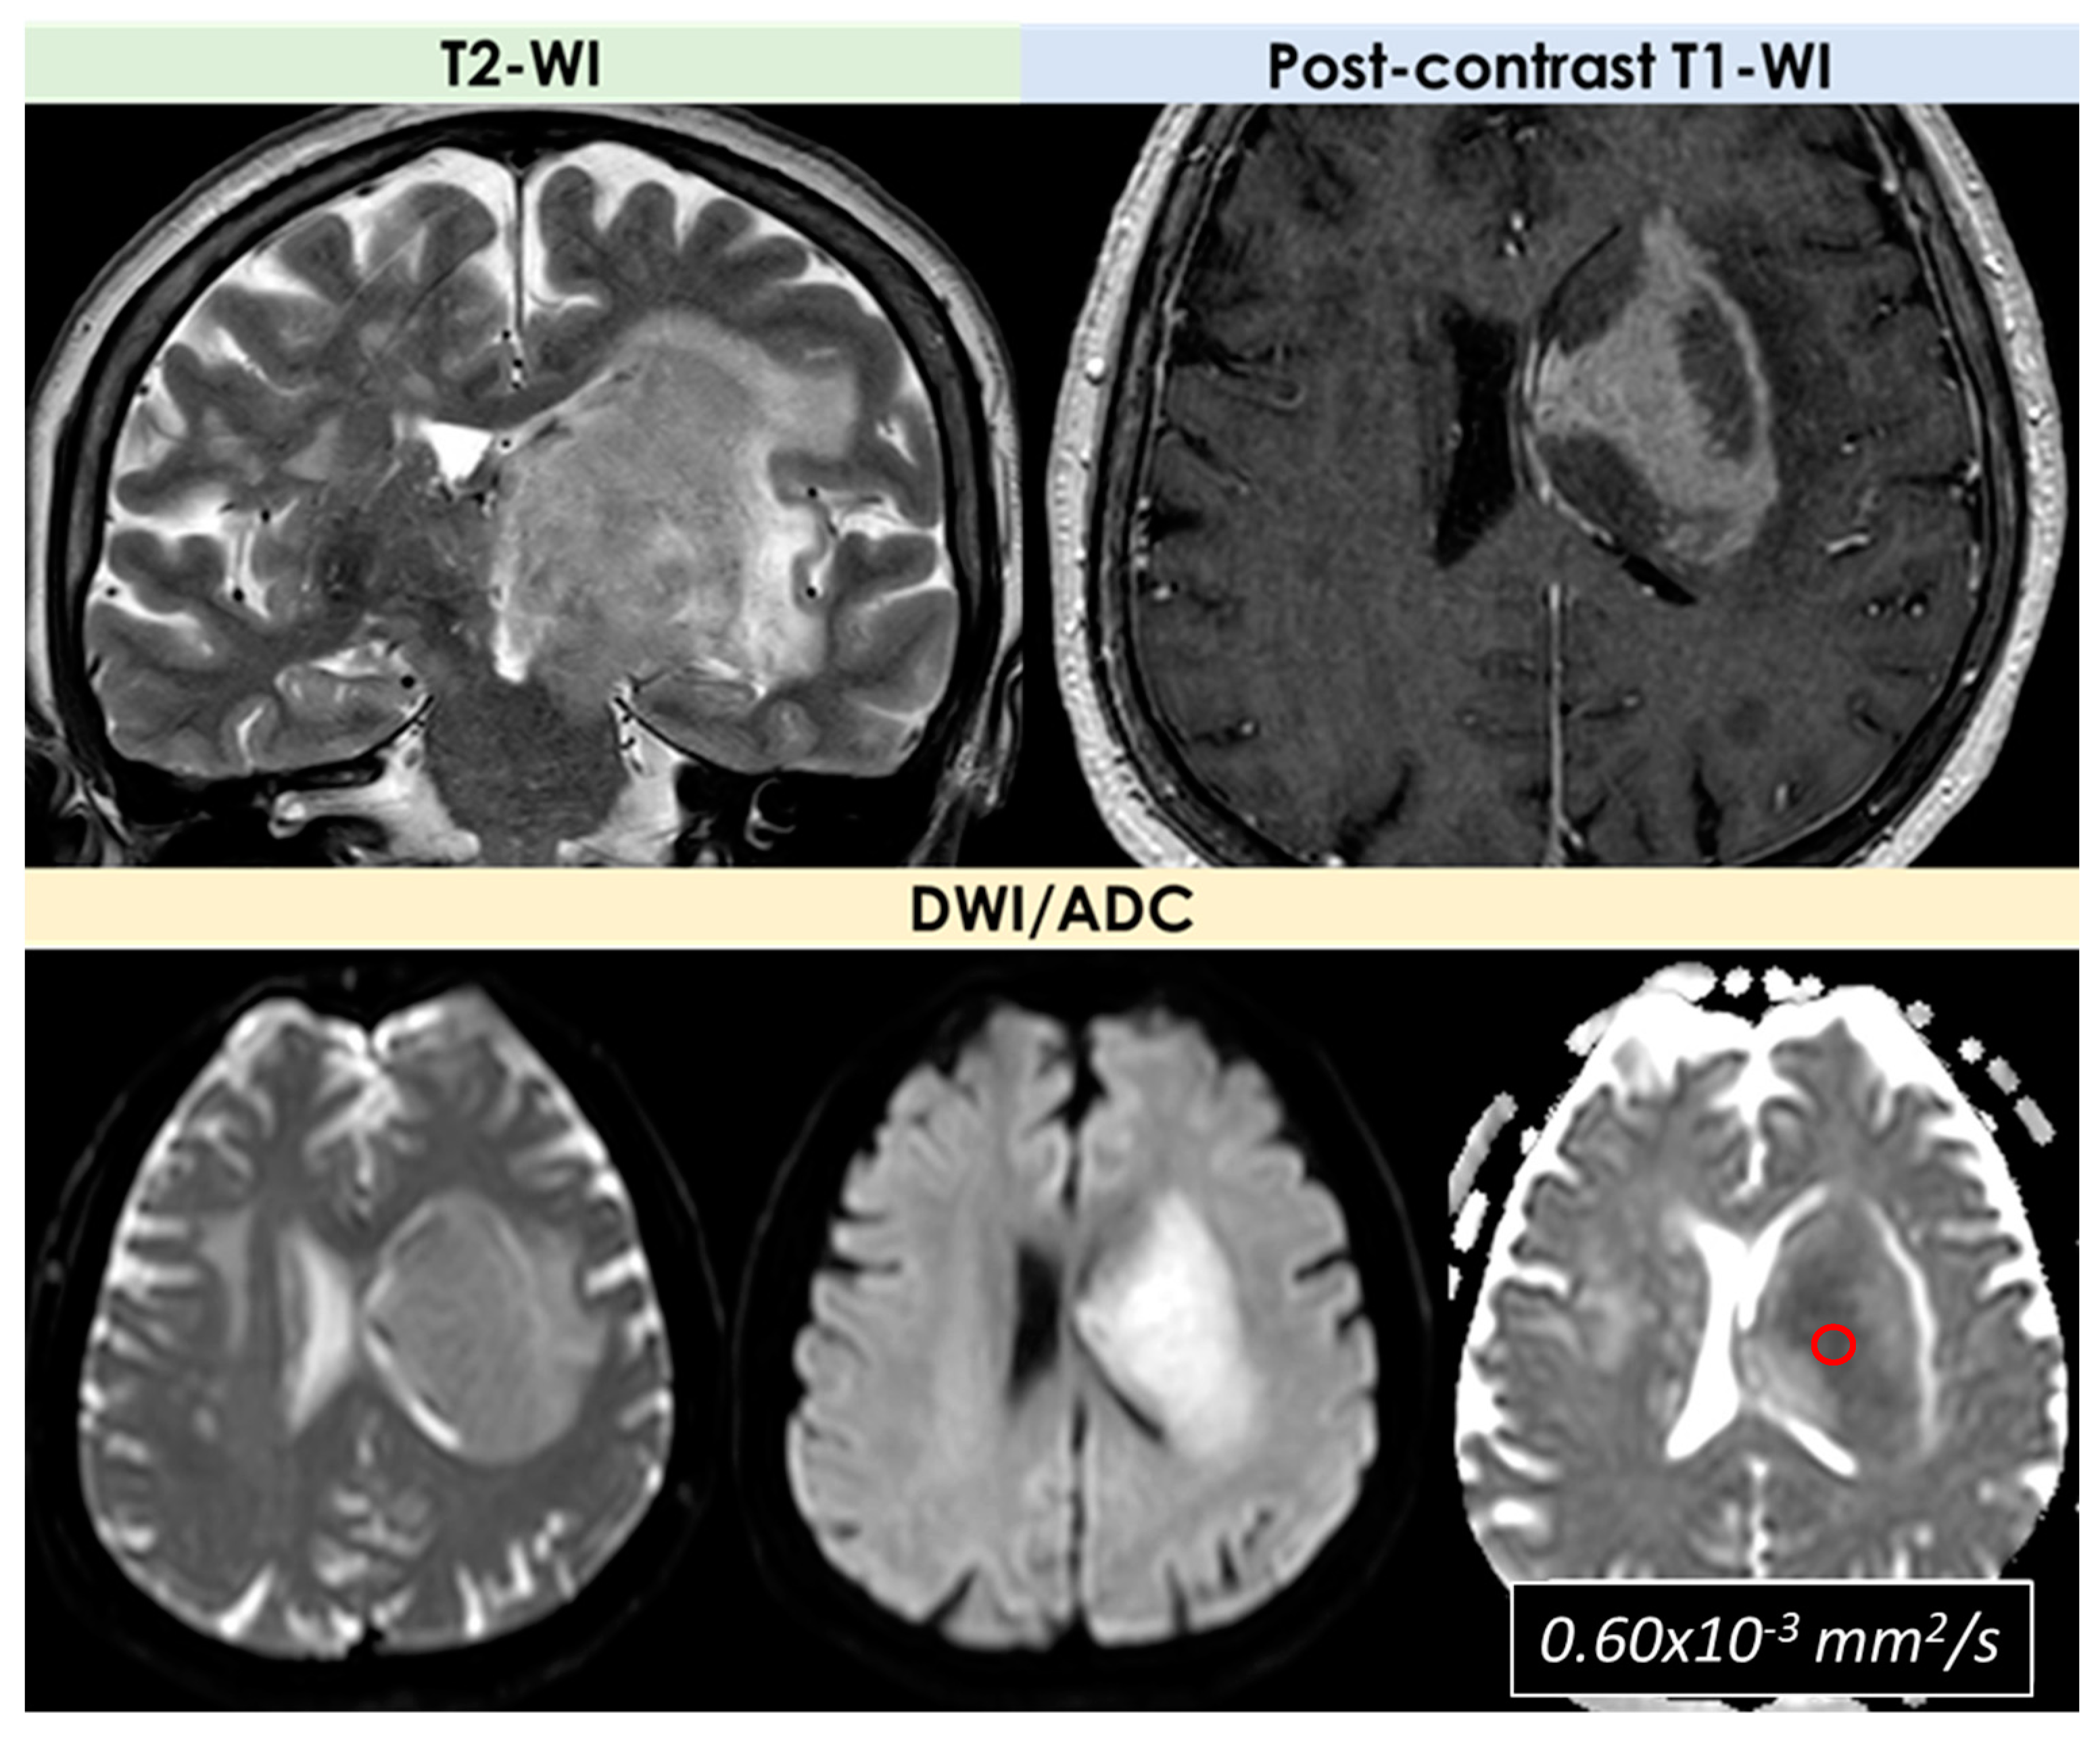

- Signal features: T1-Weighted Imaging (T1-WI) hypointense signal and intermediate to hyperintense signal on T2WI without diffusion restriction; intralesional microhemorrhages (small linear or punctate patterns on either Gradient Recalled Echo (GRE-T2*) or Susceptibility Weighted Imaging (SWI)) in 8/10 (80%) patients;

- Signal features: the single lesions were an enhancing mass with edema in the suprasellar area with decreased signal on apparent diffusion coefficient (ADC) map, and a focal edematous mass-like lesion (2.1 cm) with T2-high T1-low signal lesion, gyral swelling, and increased ADC, respectively;

| DWI/ADC | Hyperintense on DWI/hypointense on ADC maps Decreased FA values in lesions | High ADC values in center of lesion and relatively low ADC values in periphery of lesion Threshold for the minimum ADC value for distinguishing TDLs from PCNSL is 0.556 × 10−3 mm2/s | Hypointense in DWI and ADC | Hypointense on DWI and ADC | “Eccentric target sign” consisting of an eccentric nodule along the rim of an enhancing lesion on T1-WI ADC > 1.6 × 10−3 mm2/s suggestive of toxoplasmosis |